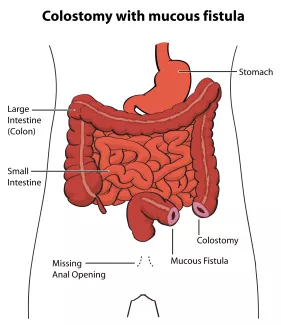

If the rectum ends high in the pelvis and is too far from the skin, surgical repair will be done in stages. First a stoma, or connection of the colon to the skin on the abdominal wall will be created.

An opening, called the colostomy, will allow stool to pass into a bag. The second opening is called the mucous fistula and allows the closed end of the rectum to drain fluid or mucous as needed. After this operation, the baby can go home to recover and grow.

Before the second operation, where an anal opening will be made in the correct location, within the anal sphincter, your child may need to have a radiographic study called a distal colostogram to help prepare for surgery. The study helps to determine the distance from the blind end of the rectum to the skin and if there is a fistula.

If a fistula is found to the urogenital system, it will be closed at the time of the second operation. The stoma will be left intact, and not closed, to allow the new anus to heal. After this operation, the baby can go home to recover.

About a couple of months after the new anus is created, the stoma will be closed in a third operation. The baby will then pass stool through the new anus. It is very important to continue the anal dilations after the stoma is closed, as directed by the surgeon.